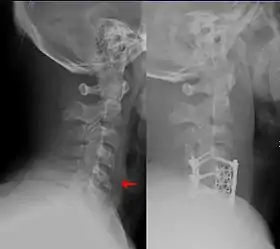

![]() This fracture of the lower cervical vertebrae is one of the conditions treated by orthopedic surgeons and neurosurgeons. | |